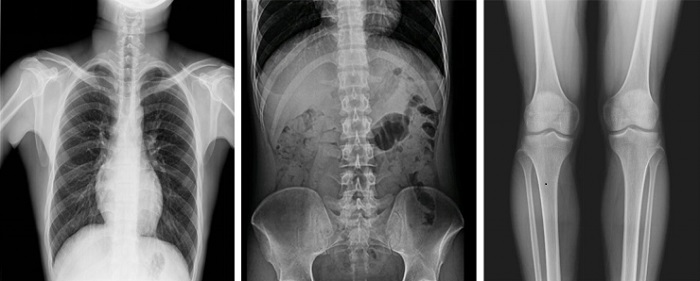

以普利德多功能動態(tài)平板DRF為例,一改傳統(tǒng)DR只能進(jìn)行盲拍的模式,通過多角度動態(tài)實(shí)時影像實(shí)現(xiàn)全方位觀察,當(dāng)疑似病灶出現(xiàn)時,進(jìn)行瞬時高清點(diǎn)片,精準(zhǔn)捕獲高清病灶圖,大大降低漏診誤診率。同時,17×17英寸大幅面成像,能對胸部、腹部等部位實(shí)現(xiàn)大范圍全覆蓋,更便于醫(yī)生觀察和診斷。